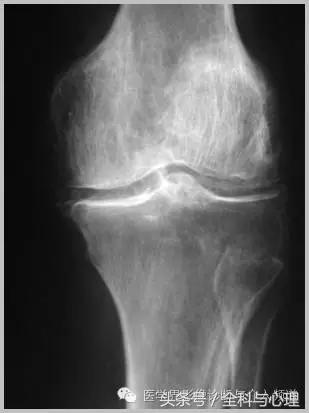

常见于膝盖、耻骨联合、臀部、尺骨三角纤维软骨复合体、肩关节。

半月板钙化